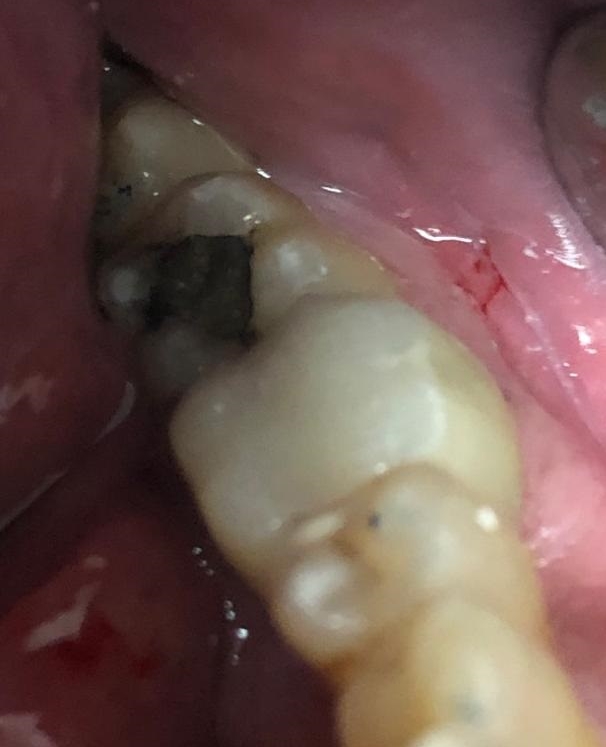

Paciente de mediana edad al que se le hizo una endodoncia con restauración de composite en el primer molar inferior o mandibular izquierdo hace varios años. Con el tiempo ha filtrado haciéndose caries en el interior de la restauración, e incluso en la raíz anterior o Mesial, en la cual se produjo una fractura vertical. Esto provocó el inicio de molestias en el paciente y es cuando acude a la clínica del Doctor Faus. Tras estudio radiológico, y ante el estado y molestias de la pieza, se le propone exodoncia y colocación de implante para restauración definitiva. El paciente con la explicación realizada sobre los implantes dentales manifiesta sus temores y pregunta sobre otras posibilidades menos traumáticas y mas económicas.

Como la raíz del molar que esta con la fractura vertical es la raíz anterior se le explica que hay que separarla de la posterior. A continuación procederíamos a realizar la extracción de ésta y la limpieza de la fibrosis de la zona. Dejamos curar el tiempo necesario para que cicatrice la zona anterior y ver cómo va evolucionando la raíz posterior.